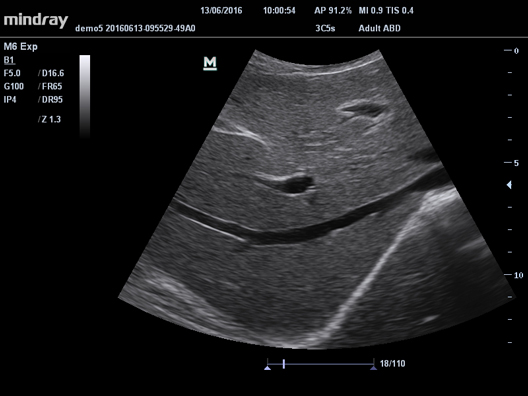

iClear

Визуализация с подавлением зернистости. Улучшение качества изображения за счет автоматического распознавания структуры тканей.

iClear

Визуализация с подавлением зернистости. Улучшение качества изображения за счет автоматического распознавания структуры тканей.